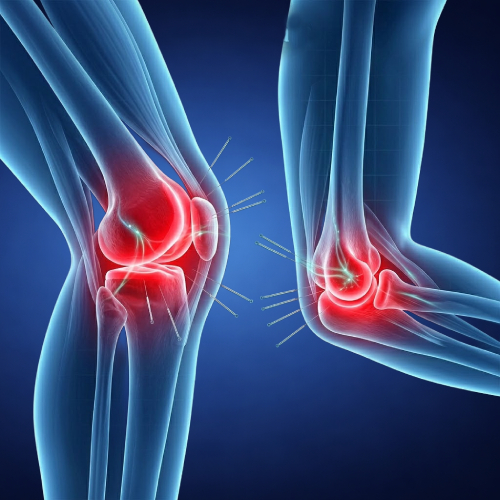

Conditions Where Acupuncture Can Help

Acupuncture is often chosen to support a variety of physical and wellness-related concerns.

Supports Pain Relief

Helps reduce recurring discomfort through highly precise, natural stimulation.